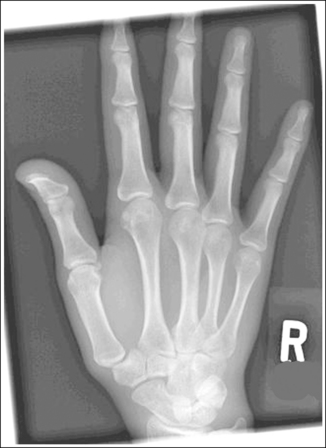

See Figure 4-22 and Box 4-8.

The digits and metacarpals demonstrate a PA projection. The soft tissue outlines of the second through fifth phalanges are uniform, the distance between the metacarpal heads is equal, and the same midshaft concavity is demonstrated on both sides of the phalanges and metacarpals of the second through fifth digits.

• A PA projection of the hand is obtained when the patient fully extends the hand and rests the palmar surface flat against the IR (Figure 4-23).

• PA versus external oblique hand position. If the hand is not fully extended but is slightly flexed, it often relaxes into an external PA oblique projection when it is resting against the IR. A PA oblique hand projection is signified by slight superimposition of the third through fifth metacarpal heads and unequal soft tissue thickness and midshaft concavity on the sides of the phalanges. The metacarpals also show unequal midshaft concavity and spacing (see Image 20). Abducting the patient's arm and placing the forearm and humerus on the same horizontal plane, with the elbow flexed 90 degrees, assists in preventing an externally rotated PA oblique projection and will best demonstrate the wrist. This is important if a wrist condition is causing radiation hand pain. When the patient has been positioned in this manner, the ulnar styloid appears in profile on the image. Internal rotation of the hand is seldom a problem, because the thumb prevents this movement.